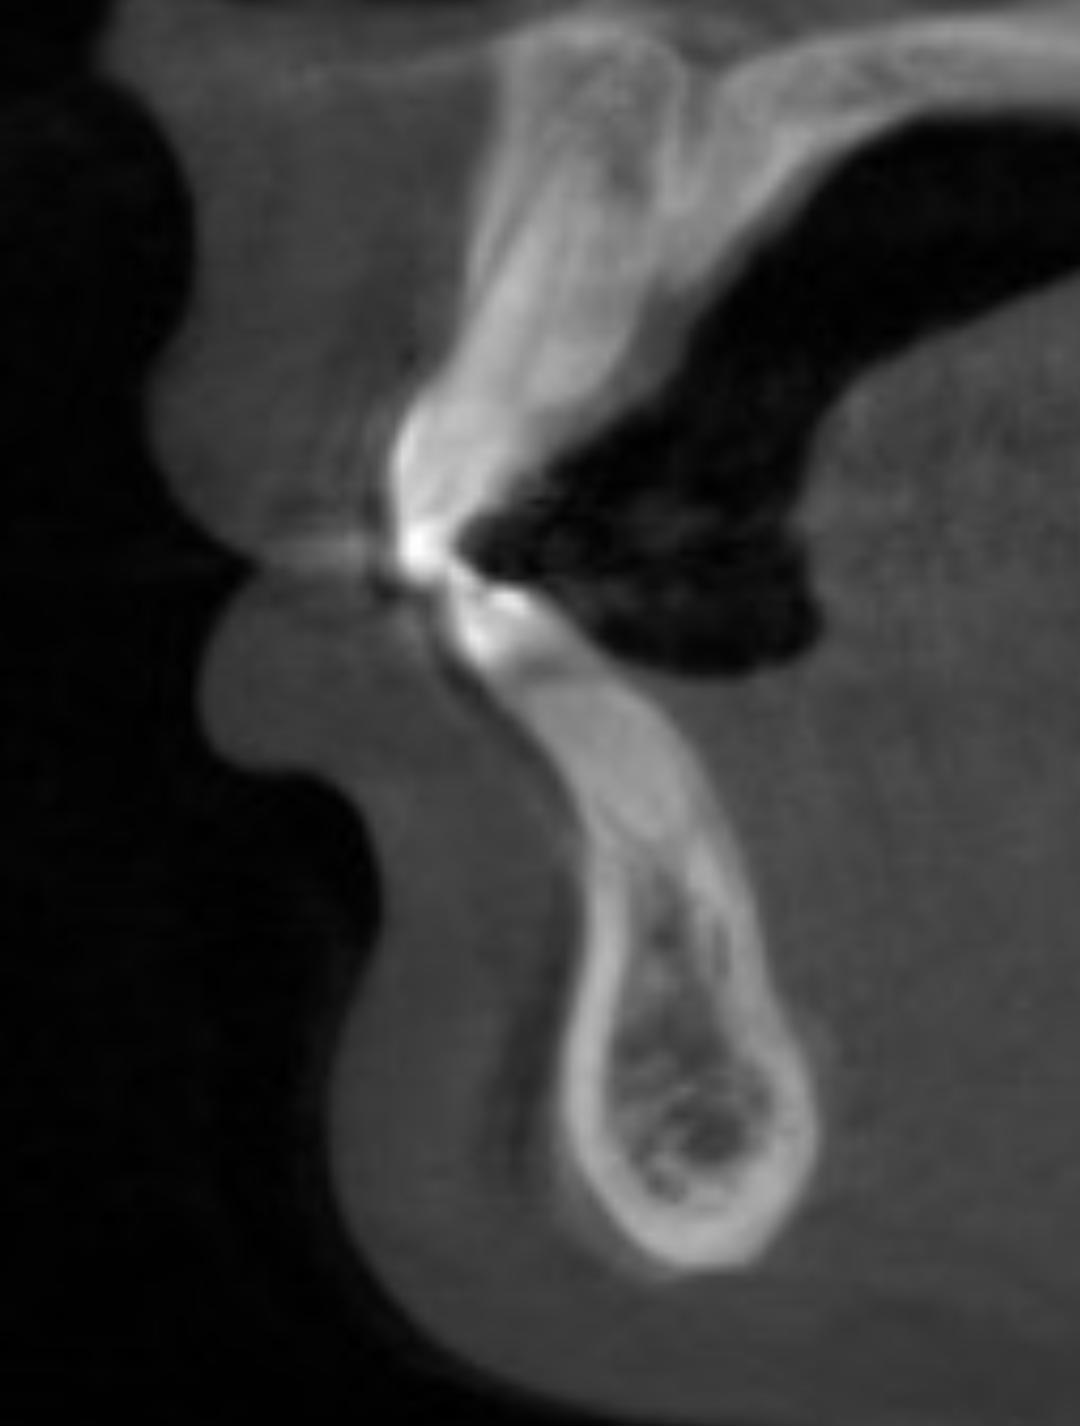

Your mandible is recessed and your airway oropharynx cross section looks very small. Just imagine when you relax and lay down, your tongue goes back and blocks your airway even more.

The philtrum seems quite tall in the ct which may explain why your teeth show less. You have room for advancement in both jaws

Yes. Your lower front teeth are inclined forward